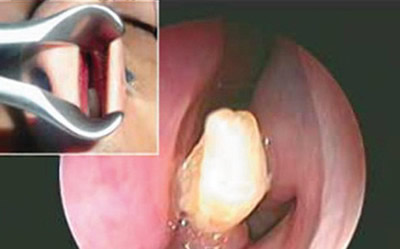

2、鼻子里的牙齿

流鼻血是一件非常常见的事,但对于一个经常流鼻血的男子来说,造成这一现象的原因竟然是因为他的鼻子里长了一颗牙齿。

今年22岁的SaudiArabia近3年来,每月都会流一两次鼻血,于是他去看了医生。结果医生在他的鼻腔内发现了一颗乳白色半英寸长的牙齿。牙医对这一情况的看法是这大概是一颗多余的不知道为什么长在鼻子里的牙齿,然后帮其动了手术摘除了这颗牙齿。

值得一提的是,Saudi的嘴里却长着一整副完整的牙齿。